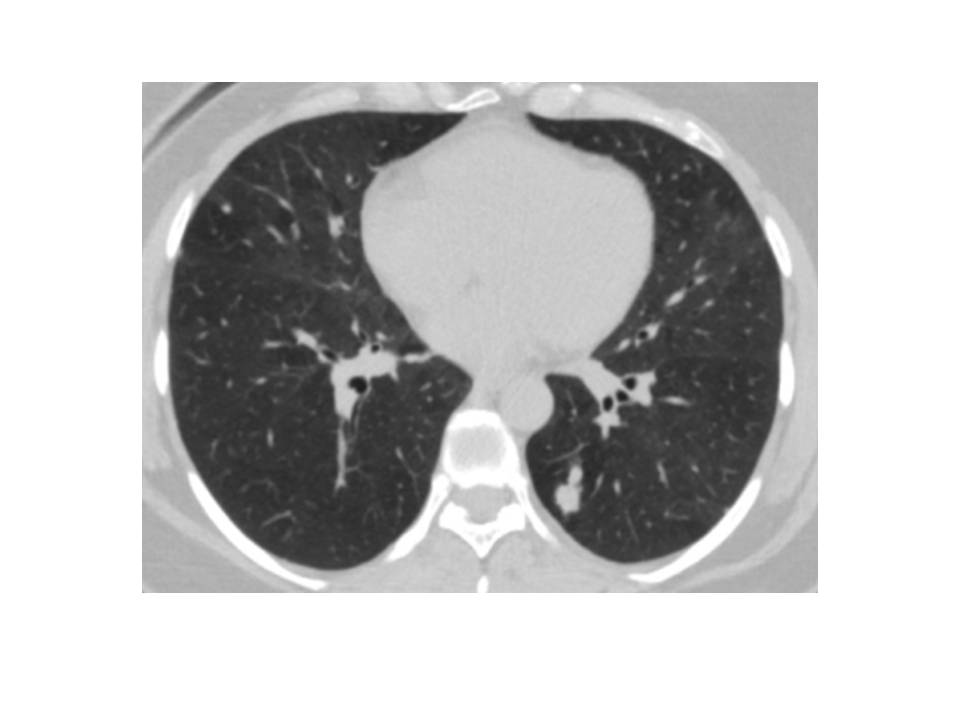

In April 2022, a 45-year-old female patient had Covid 19 and in thorax computed tomography (CT), a 1 cm diameter nodule was discovered in the left lower lobe (Figure 1). Bronchoscopic and cytological testing revealed no abnormalities. Positron emission tomography-CT was performed and late fluorodeoxyglucose uptake (FDG) SUVmax was 2.7. Malignancy could not be ruled out and left lower wedge resection was performed on the patient. In frozen section, it was shown to be benign. The final pathology report revealed that the patient had primary myxoid pulmonary sarcoma. The patient had a lower left lobectomy. At 6 months following surgery, the patient is doing well and there has been no recurrence.